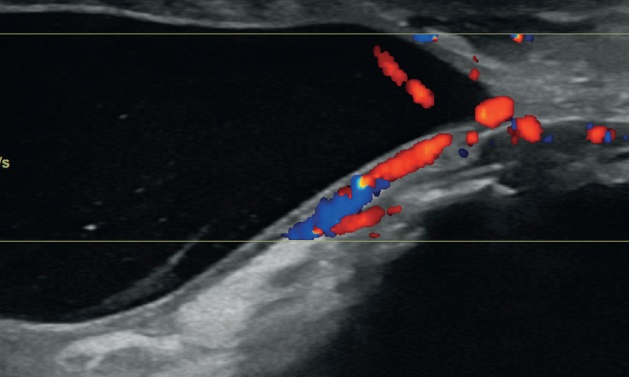

심한 수신증의 경우, 압력으로 인한 신장 실질의 괴사로 조직 손실이 상당히 발생할 수 있습니다. 극단적인 경우, 현저히 확장된 신우를 둘러싸는 얇은 테두리 조직만 남을 수도 있습니다(그림 3). 또한 신문(hilum)에서 신장 피막 쪽으로 뻗는 여러 개의 고에코성 선형 띠가 보일 수 있는데, 이는 신우 사이 격막(interdiverticular septa)을 나타냅니다(그림 3c).

초음파 소견으로는 신우 내 고에코성 잔사(찌꺼기), 수신증, 정상 신장 구조 소실 등이 포함됩니다(그림 4).